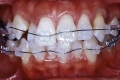

マルチブラケット終了時